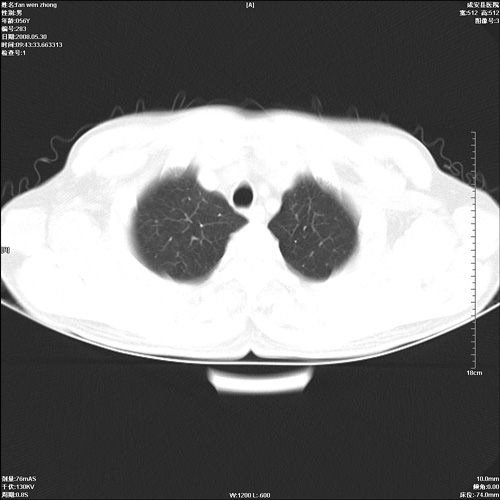

病人 男 56岁 一周前高热,体温达39-40度,经抗炎治疗后,体温渐降,达37,5-38度,轻微咳嗽,胸部不适 查白细胞为1.3万 行ct检查,请分析。

双肺内可见多发结节状病灶,并见小空洞,病人高热,白血球增高,应该是典型的迁徙性肺脓肿(多为金黄色葡萄球菌感染)。查一下口腔等其它部位有无感染灶。

双肺内可见多发结节状病灶,并见小空洞,病人高热,白血球增高,应该是典型的迁徙性肺脓肿(多为金黄色葡萄球菌感染)。建议治疗后复查.